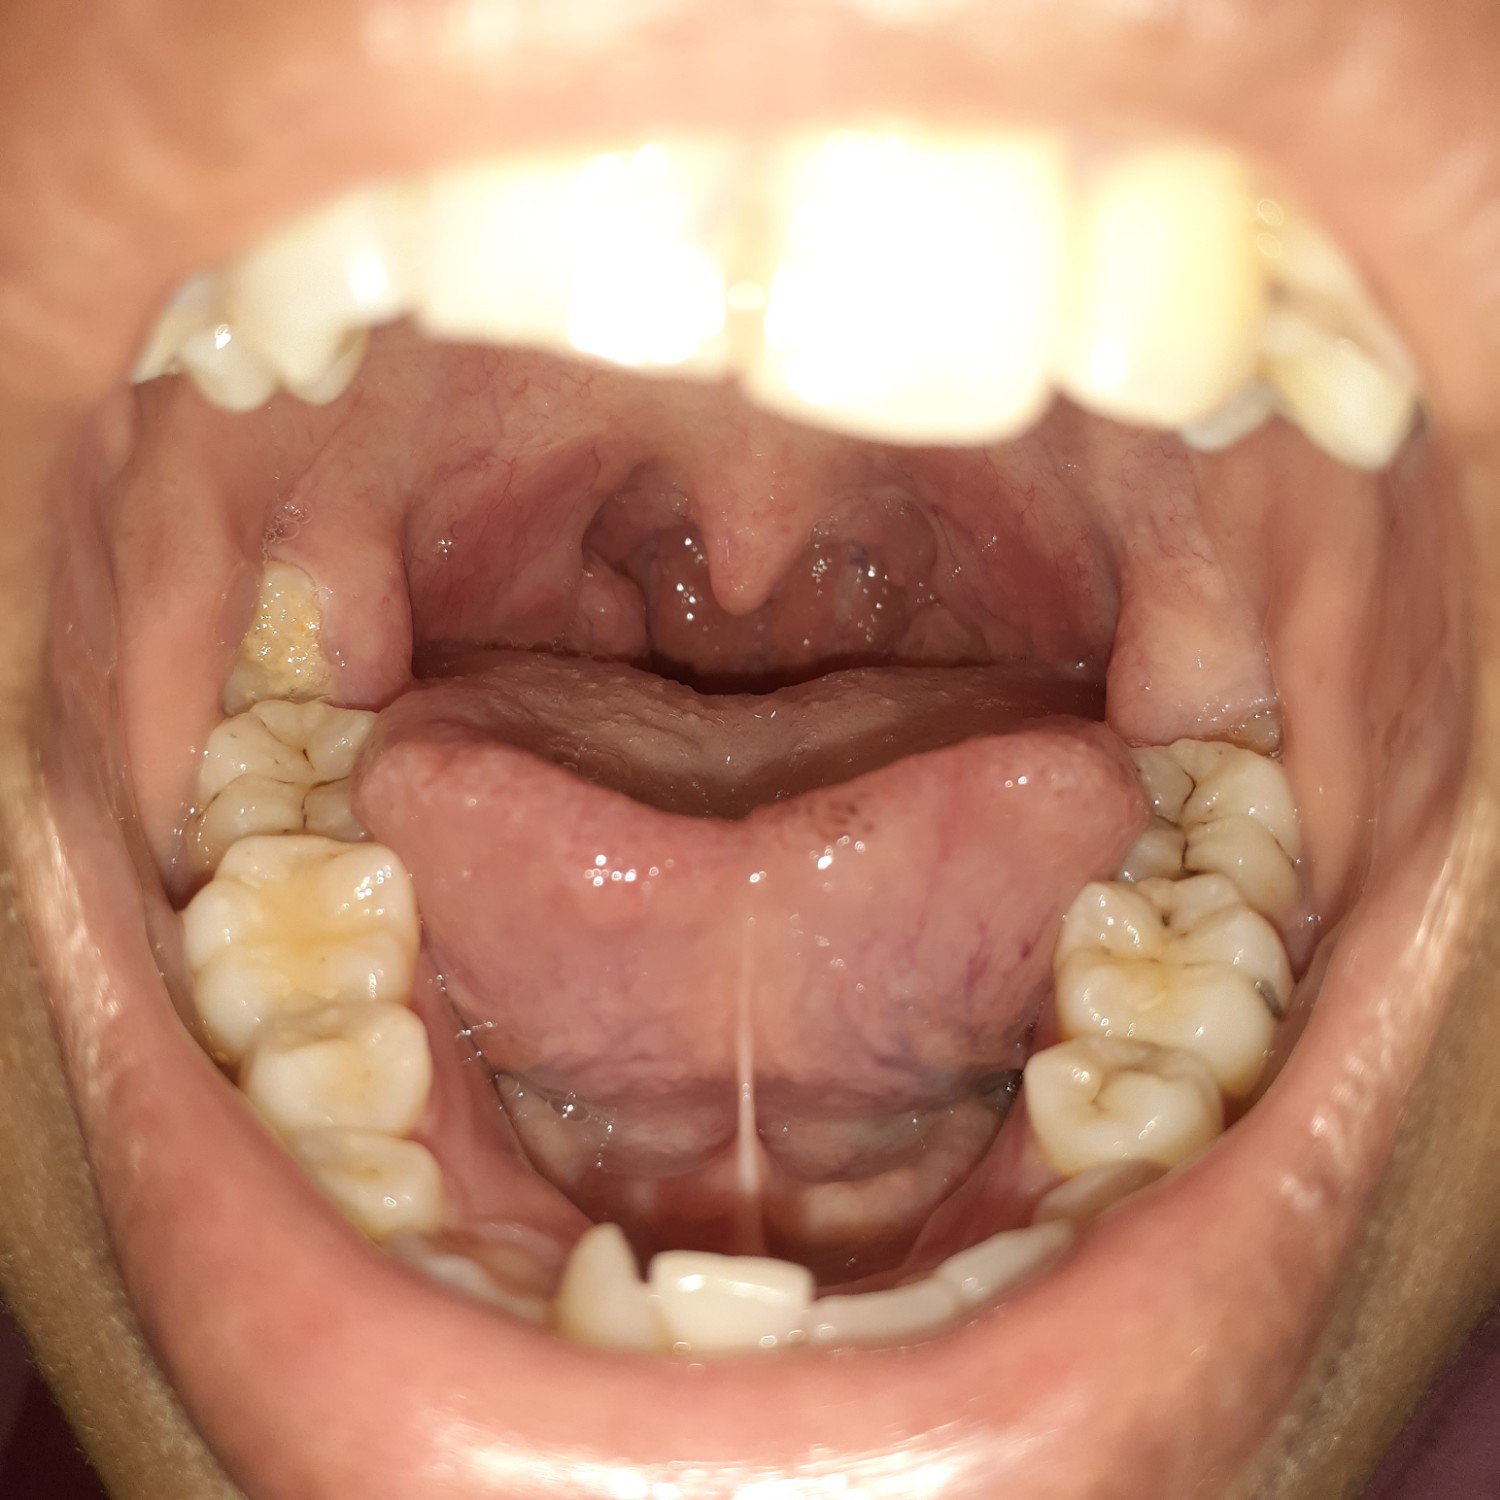

คอเป็นแบบนี้ปกติมั้ยค่ะ